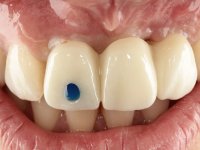

The surgical implant exposure and the healing screw placement proved to be a negative surprise regarding its position. Since the proposed removal of the implant was refused, we advanced to its provisional rehabilitation. An open tray impression technique was done, and a screwed abutment with a coronal and gingival component and an acrylic crown were made in the laboratory, using these two components. The provisional crown was placed in the mouth until a final decision was made. Six years passed before the patient returned to the clinic with an abscess on tooth 1.1. The choice to remove teeth 1.1 and 2.2 was made, to create a provisional 3-element bridge with a net to be adhered to the adjacent teeth. Surgery was planned and performed, placing the two implants at the site of 1.1 and 2.2, and the implant at the 2.1 site was cut with the objective of submerging it, while adequate tissue regeneration was performed (Surgical Work performed By Dr. Manuel Neves). During osseointegration, the patient used the fixed provisional bridge. A first impression was made for confection of a zirconia screwed provisional bridge, which worked the soft tissues for twelve weeks. The definitive impression was made with the individualisation of custom impression copings. Final rehabilitation was done with ceramized abutments, and also a bridge with zirconia infrastructure and ceramic cover. Due to the inclination of the implant placed at the site of tooth 1.1, the bridge required cemented fixation.